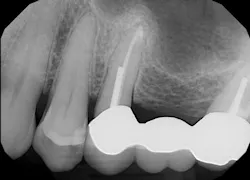

After using a round burnisher and blow test to determine that there was no perforation to the sinus and the membrane was still intact, the laser was used at a spot size of 1.25 mm, on low power mode, and without mist or air to debride the medial superior area of the bony defect. X-rays were taken following immediate placement of bone-graft material to display the site after using Solea to remove bone and granulation tissue (figures 6 and 7). The entire procedure, including the bone graft, took approximately 40 minutes from start to finish.